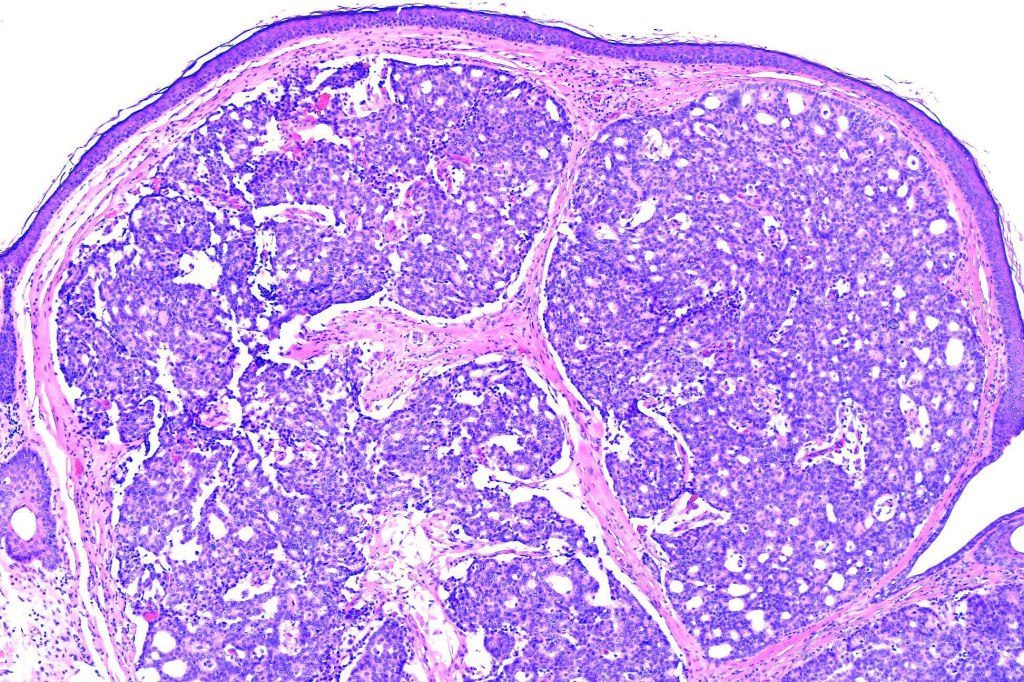

•Mucinous carcinoma is characterized by epithelial islands dispersed in a rich mucinous stroma

•EMPSGCa– multiple nodules of uniform epithelial cells with vesicular nuclei & small nucleoli

•Cyst formation sometimes evident

•Papillae & cribriform pattern sometimes evident

•+/- invasive mucinous carcinoma (50%)